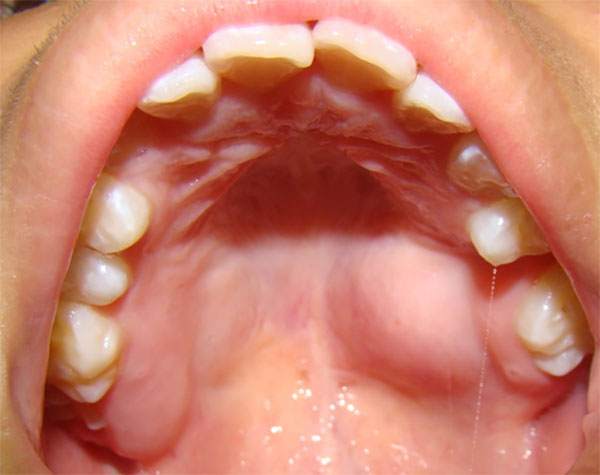

A la anamnesis no refirió antecedentes médicos personales ni familiares de importancia. Al examen clínico extraoral se apreció simetría facial, sin adenopatías cervicales palpables. En la exploración intraoral presentó una lesión en el lado izquierdo de la bóveda palatina, en la zona molar, de aproximadamente 2 cm. de diámetro, de consistencia firme, bordes definidos, del mismo color de la mucosa, con base amplia, superficie lisa, indolora a la palpación, asintomática, sin desplazamiento, ni hemorragia, la paciente no refirió disfagia, odinofagia ni disnea (Figura 1).

|

Figura 1

Lesión única en paladar cubierta por mucosa sana. Fuente propia |